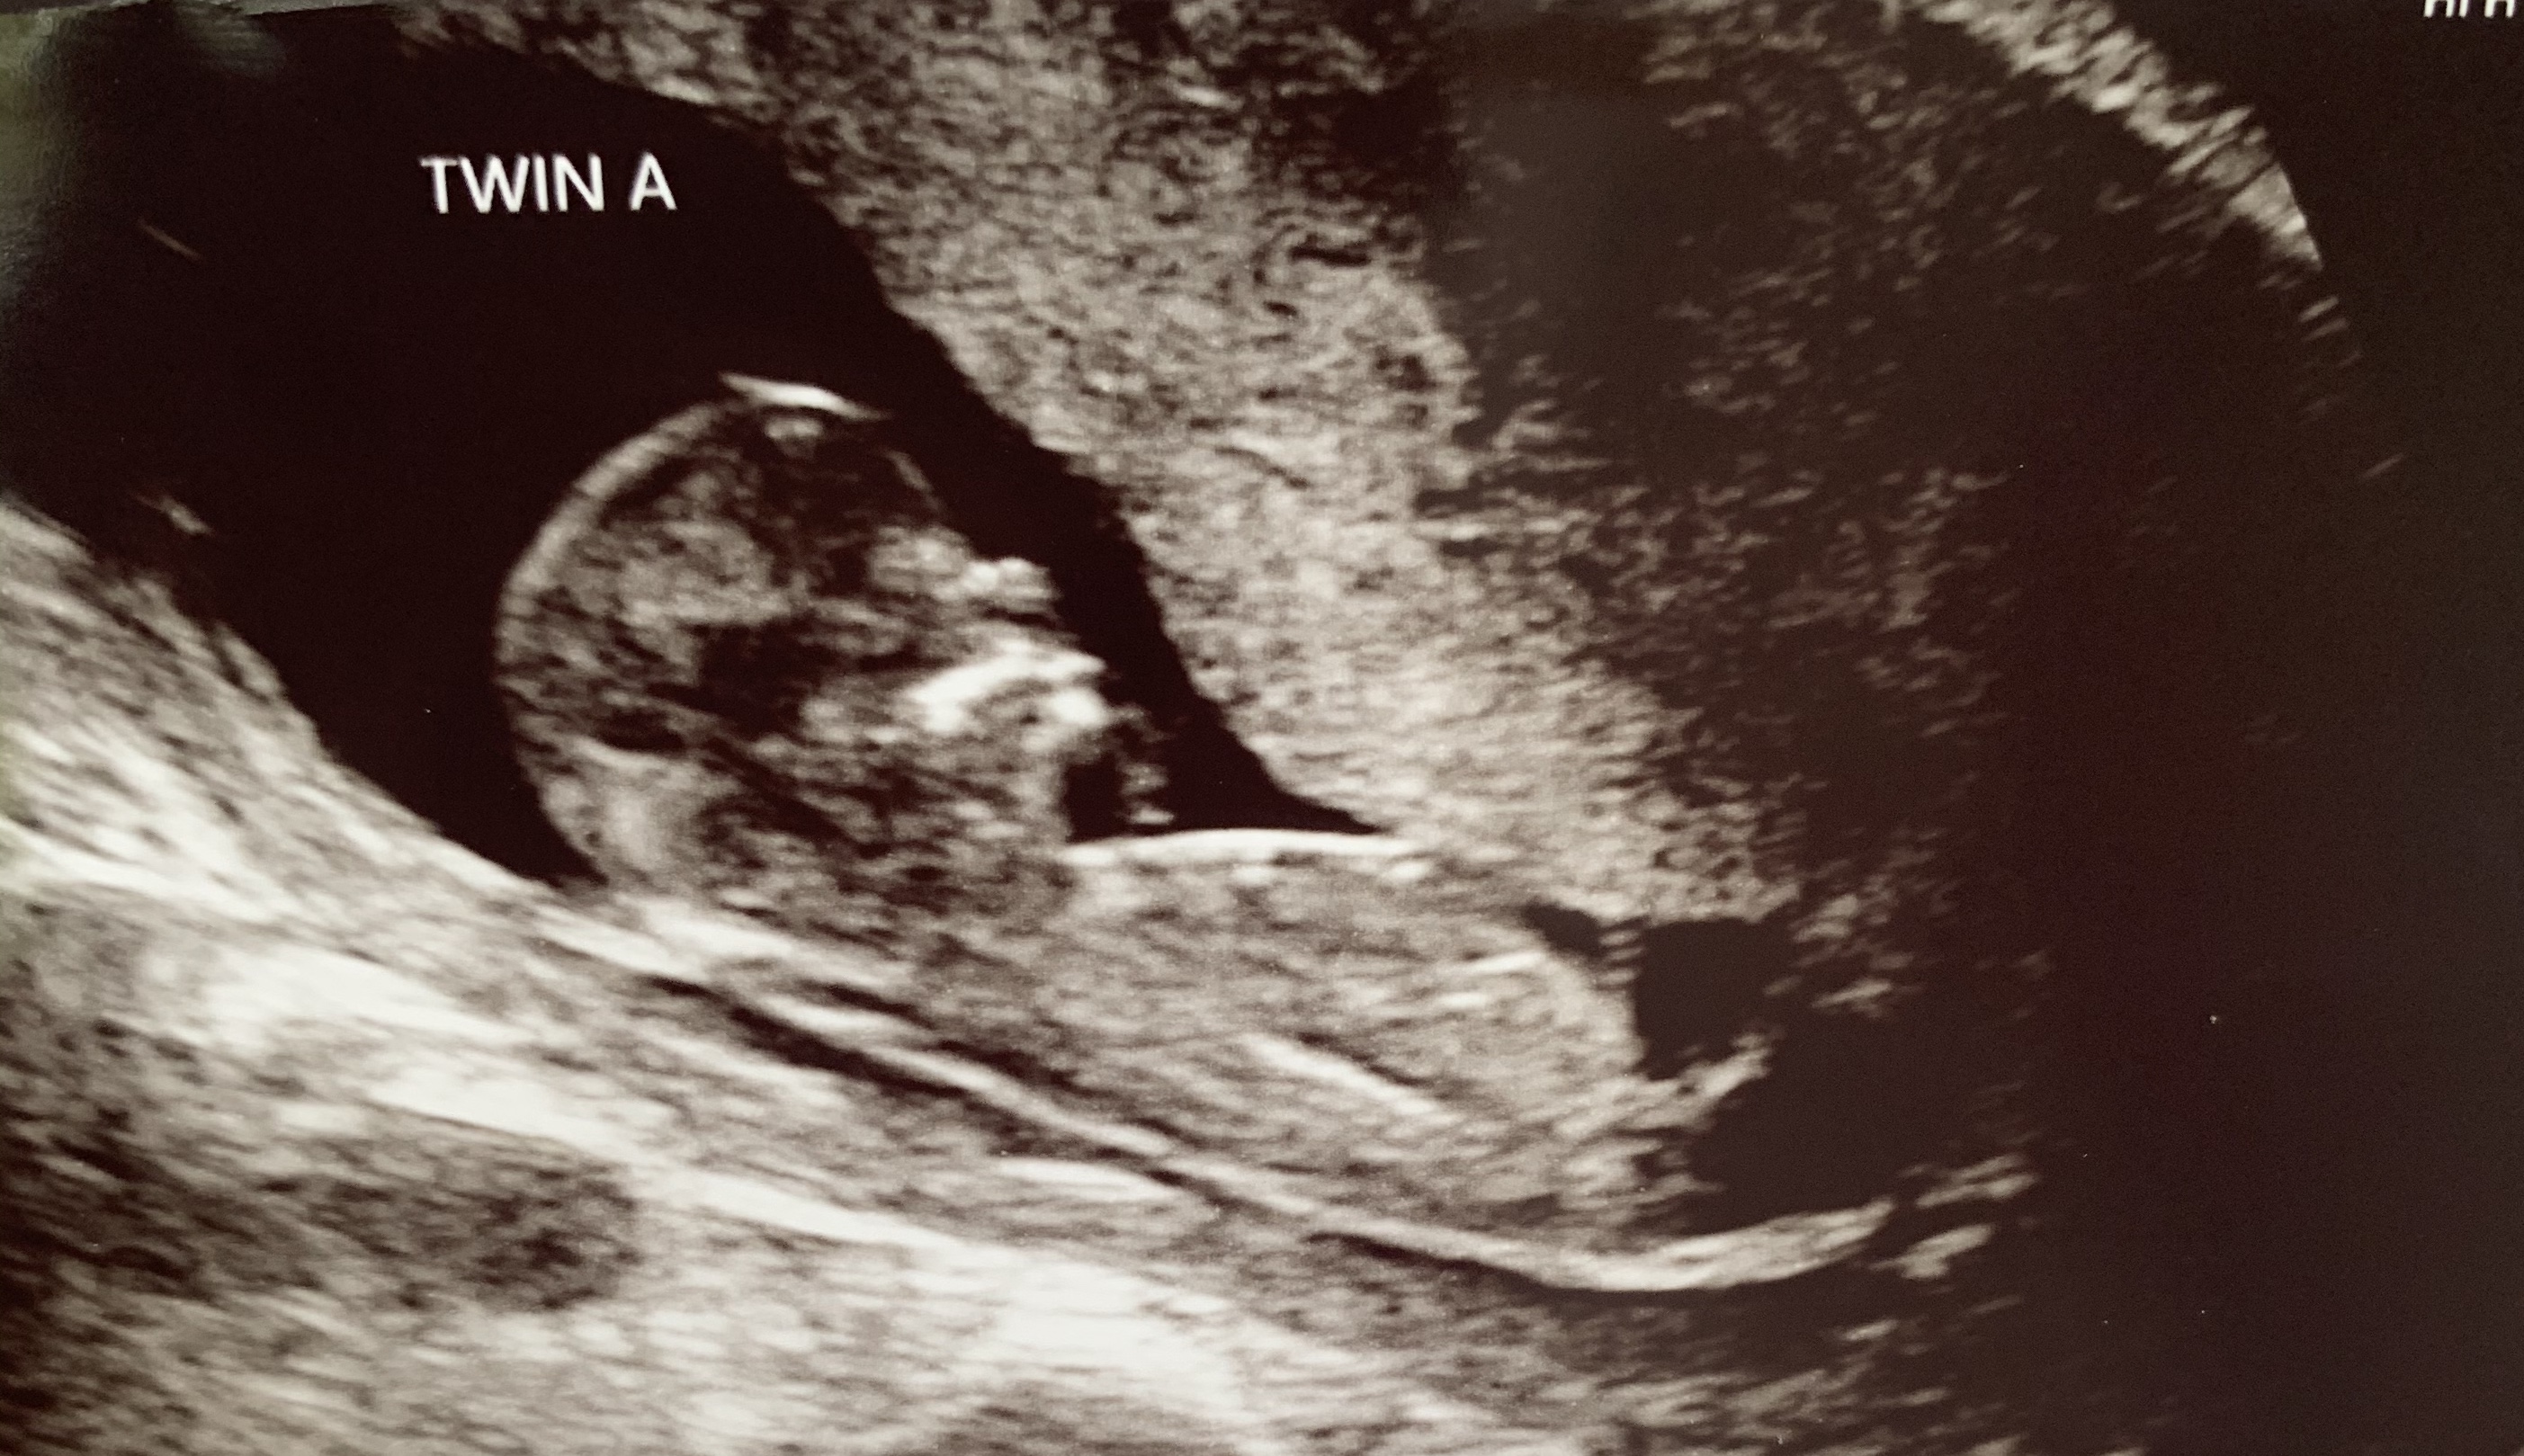

Back with some new ultrasound pics! 12w3d here :)

While earlier than I like to guess I'll give a guess of Twin A being a boy and Twin B being a girl.

Thanks for the guess! My gut says one boy and one girl too, but we'll see! :)

Well, blood test confirms one boy and one girl! We'll have to wait until the next scan to confirm which twin is which, but looks like you were right. :)

You were right! Twin A is the boy; twin B is the girl. :)